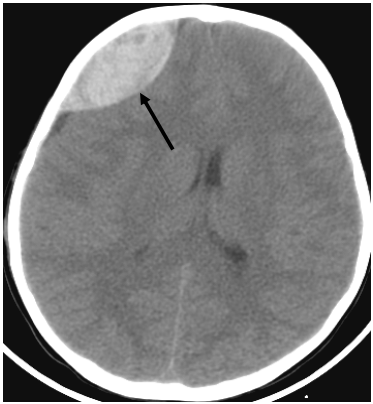

72 頭部外傷患者,緊急電腦斷層攝影的影像如附圖,箭頭所指的是:

(A)急性硬腦膜上腔血腫(acute epidural hematoma) (B)急性硬腦膜下腔血腫(acute subdural hematoma) (C)慢性硬腦膜下腔血腫(chronic subdural hematoma) (D)腦挫傷之出血(contusion hemorrhage)